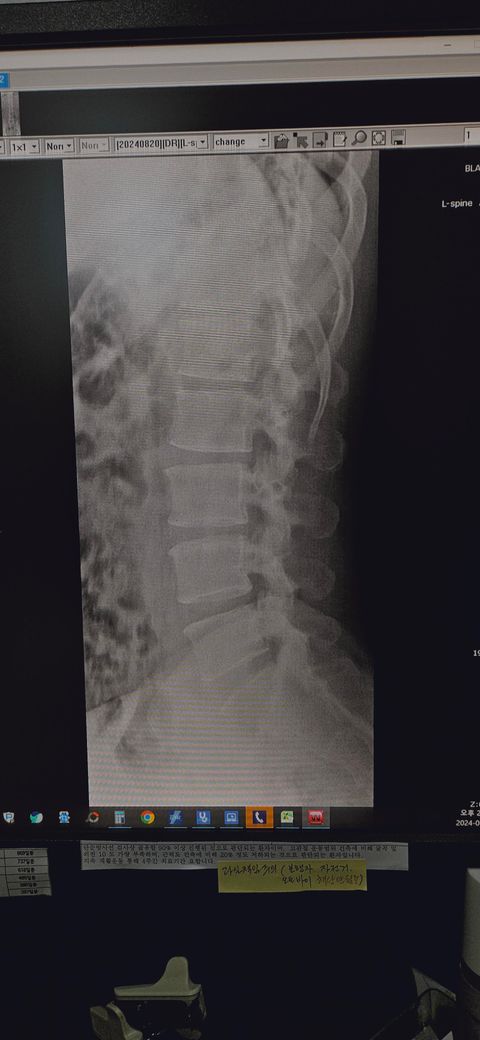

• 2번 째 사진

사진으로 보아서는 정상 허리에 비해 허리의 만곡이 완만해져 있으며 척추도 약간 휘어져 있으며 골반도 틀어져 있는 것 같이 보입니다.

허리를 전만 커브고 약간 적은 편이라 경도의 일자 허리 정도라고 볼수는 있겠으나 심해보이진 않고 요추전만 운동 해주고 코어운동 및 중둔근 위주 운동해주면 충분할것 같습니다.

어느정도 일자허리가 진행되고 있는 것으로 보입니다. 일자허리는 쉽게 말해서 허리가 약간 구부정하게 되어있는 상태로 이해하시면 되겠습니다. 업무환경이나 생활습관등에서 몸의 중심이 앞으로 굽혀지거나 쏠리는 등의 자세습관이 있으시다면 수정을 위해 업무환경을 변화하기 위해서 의자의 높낮이나 책상과의 거리를 변경해보시는 것이 좋겠고, 척추의 유연성을 위해서 꾸준하게 운동과 스트레칭을 해보시는 것이 좋겠습니다. 전문의와 상의 후에 필요시 도수치료를 받아보시는 것도 좋겠습니다.

요추전만이 조금 적은편이신 하지만 치료가 필요하지는 않겠습니다.

일자허리가 있다고 하더라도 증상이 없으면 치료가 필요하지 않습니다.

지금 작성자분에게 중요한것은 평소에 허리를 굽히지 않는 요추전만 자세를 유지해주시는겁니다.

일자허리에 대해서 주의를 주는 이유는 결국 디스크에 부하가 커지기 때문입니다. 그래서 아래 보시는것과 같은 디스크와 관련된 허리 관리를 지금부터 하시는게 큰 도움이 되겠습니다. 핵심은 결국 허리 굽히는 활동을 최대한 하지 말라는겁니다.